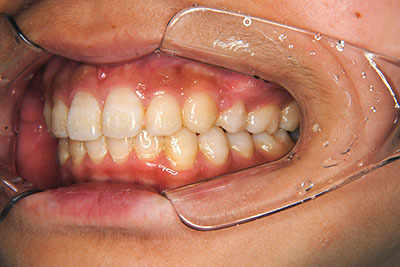

歯が乳歯から永久歯に生え変わった小学生高学年や、中高生でも矯正治療に手遅れということは全くありません。

成長中の顎の骨を矯正できたり、この時期の矯正はおとなになってから矯正治療を始めるよりも短期間で済むことがほとんどです。当院だとおおよそ1年で動的治療(マルチブラケット装置をつける期間)が終わることが多いです。